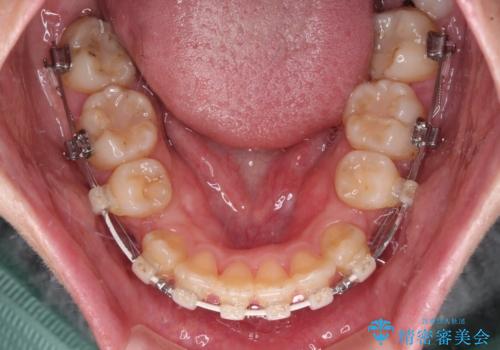

- 前歯のデコボコと突出感を気にして来院された患者様です。

上下左右第一小臼歯4本を抜歯して、積極的に口元を引っ込めるよう、ワイヤー装置にて矯正治療を行うこととしました。